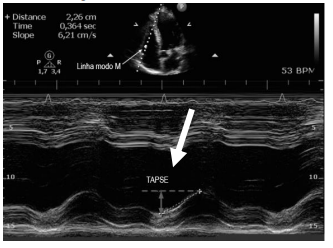

Observe a imagem abaixo:

A seta na imagem indica TAPSE que consiste: